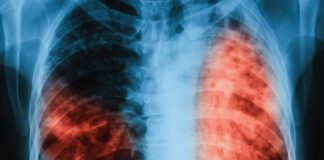

Туберколозата е инфекциозно заболяване, което в 90% от случаите засяга дихателната система, 10 % - други органи и системи – храносмилателната, пикочно –отделителната, опорно-двигателната,...